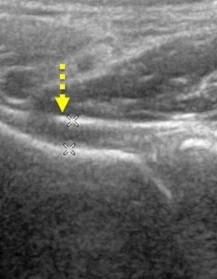

超音波下即時確認肩關節區域纖維化與增厚部位

細微針刮除沾黏部位 – 針對局部纖維化區域進行刮除(幾乎無痛)